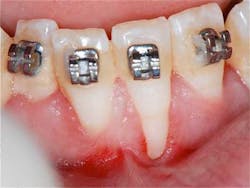

Preop: Connective Tissue Graft, Emdogain, Coronally Advanced Flap